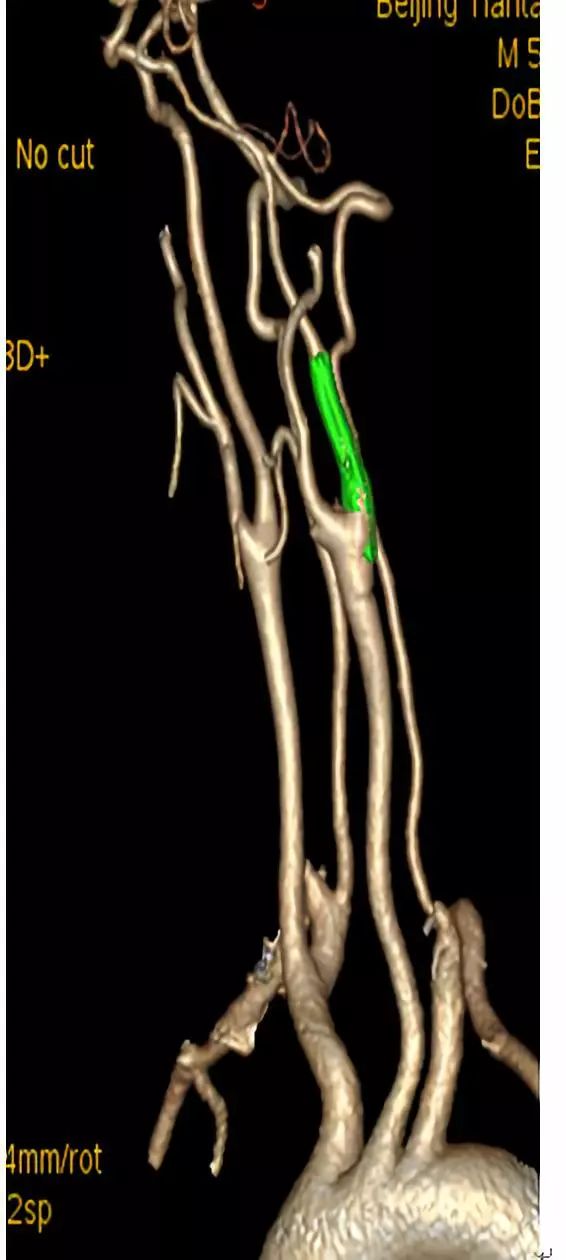

全麻下,血管造影显示右侧颈内动脉起始段完全闭塞,同侧眼动脉逆行充盈右侧颈内动脉,向近端反流到海绵窦上段同3月前的造影

先行颈动脉近端闭塞处切开并行内膜剥脱,再切口处置入动脉鞘后,用300cm 0.014微导丝交换出微导管用1.5mm×20mm gateway 行闭塞段扩张,造影显示右侧颈动脉闭塞段通畅

再使用3mm×20mm球囊行从上往下预扩张C2段三次,扩张后置入ENTERPRISE 支架4.5mm×28mm自膨支架两枚,经股动脉造影显示颈动脉全程完全畅通。复查CT未见新发梗死灶。